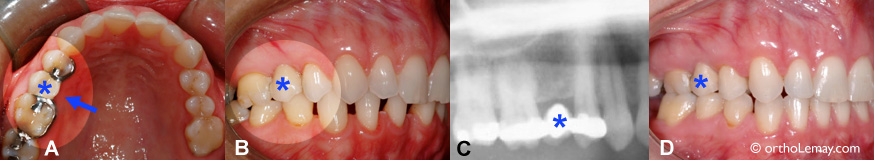

Orthodontie en présence de couronnes et ponts-1

(A et B) Avant le début du traitement d’orthodontie. Le pont comprend une partie centrale suspendue et des attaches sur les dents adjacentes. (C) Radiographie montrant le pont et l’absence de la dent sous ce pont. (D) À la fin du traitement, le pont est intacte et dans la même position. Il aurait été possible de fermer les légers espaces restants si il y avait eu une dent naturelle pouvant être déplacée plutôt qu’un pont fixe et rigide.